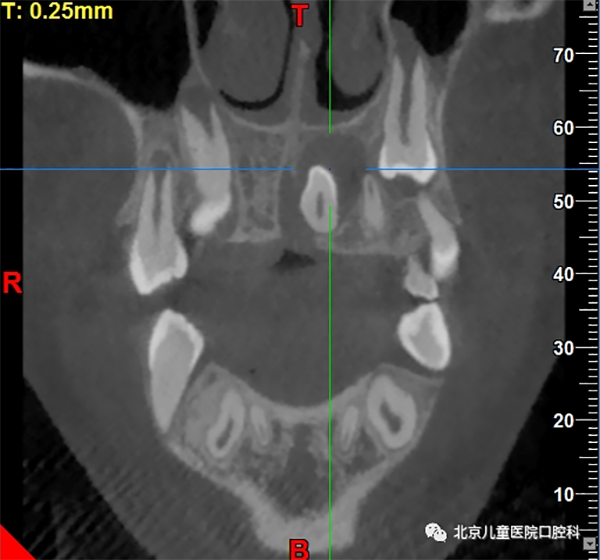

多生牙可发生在牙弓任何位置,多见于上颌前牙区,通常会占用正常牙齿在牙列中的位置,破坏正常的牙弓形态,同时,由于不具备正常牙齿的外形而缺少与正常牙齿的邻接,容易造成食物嵌塞和滞留,导致牙龈组织发炎甚至引起龋齿的发生。更有甚者,占用了正常恒牙萌出的空间,挡了正常恒牙的“路”,使得正常恒牙无法顺利萌出。

颌骨内多生牙可造成囊性变形成含牙囊肿

少数长期埋伏在骨内的多生牙,由于牙冠周围的软组织病变,会形成颌骨内的囊肿。